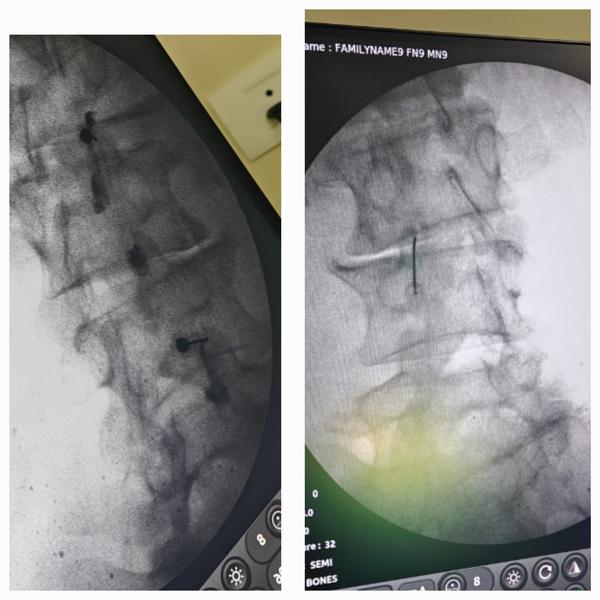

Fracture of Distal end Tibia and Fibula Fixation

Fracture of Distal end Tibia and Fibula Fixation.